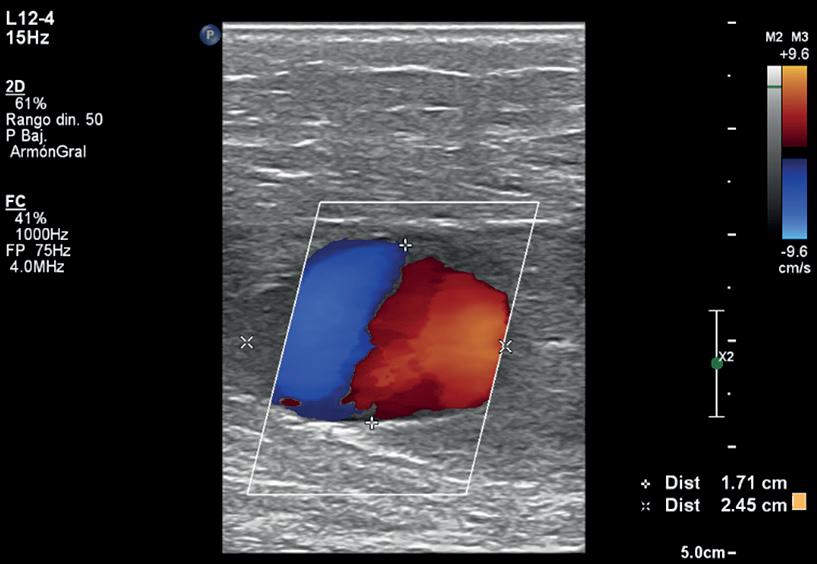

Habiendo realizado una breve introducción presentamos a continuación el caso de una paciente femenina de 46 años sin antecedentes patológicos de base, ni traumáticos, quien presentó dolor súbito a nivel de la cara posterior de la pierna izquierda de una semana de evolución que no cedió ante la ingesta de analgésicos, con posterior cambio de coloración de la piel, edema e impotencia funcional. Se decide realizar ecografía Doppler de miembro inferior izquierdo con reporte de hematoma en cara lateral interna de la pierna izquierda y dilatación vascular de paredes finas con presencia de flujo en su interior (signo de Yin-Yang), (Figura 3). Motivo por lo que se le solicita complementar con estudio de mayor complejidad para mejorar el diagnóstico.

Figura 1 Anatomía de un vaso sanguíneo arterial. Figura 2 Características diferenciales de los aneurismas, pseudoaneurismas . Figura 3 Dilatación vascular con un diámetro de 17 mm x 24 mm a nivel del tercio medio, de la cara posterior de la pierna izquierda evidenciando el signo Yin-Yang en su interior el cual representa la lesión de la pared vascular con una colección extraluminal de sangre conectada con el vaso principal, característico del estudio Doppler, el cual demuestra una curva con flujo anterógrado y retrógado a nivel del pseudoaneurisma. Figura 4 Corte axial de estudio tomográfico con contraste endovenoso de la pierna izquierda el cual demuestra dilatación de la arteria tibial posterior a nivel del tercio medio. (pseudo aneurisma roto y contenido).